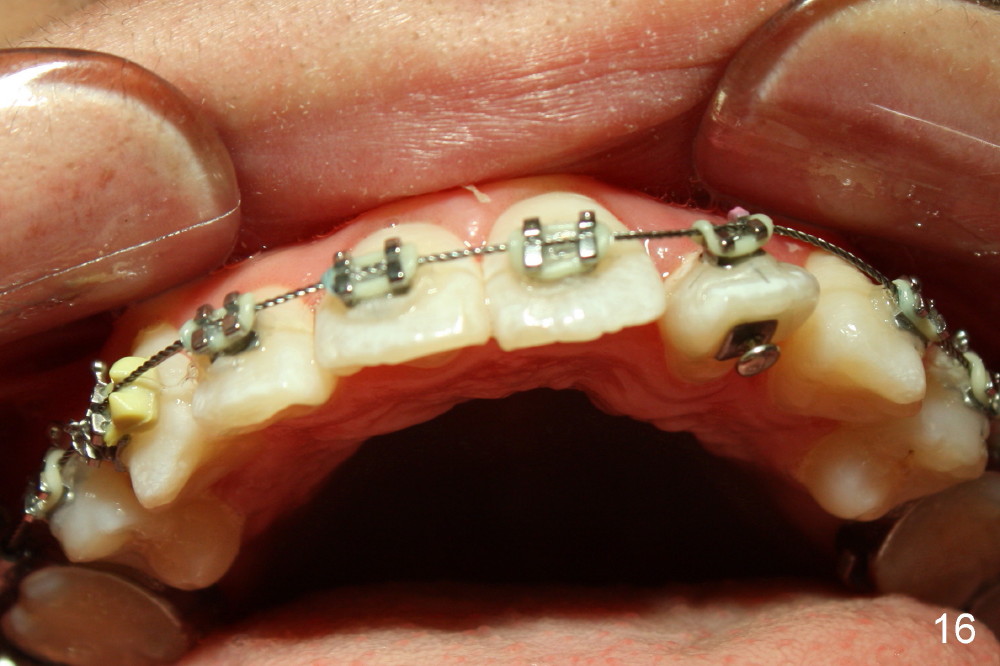

Seven months of treatment, the dental midlines coincide (Fig.13 dashed lines). Extraction spaces have been closed or being closed (Fig.13-15). UL 2 has been moved into the arch (Fig.13,15,16). But the alignment needs to be improved with arch wire sequence for a second time starting with .0175 twisted wire (Fig.13-16).